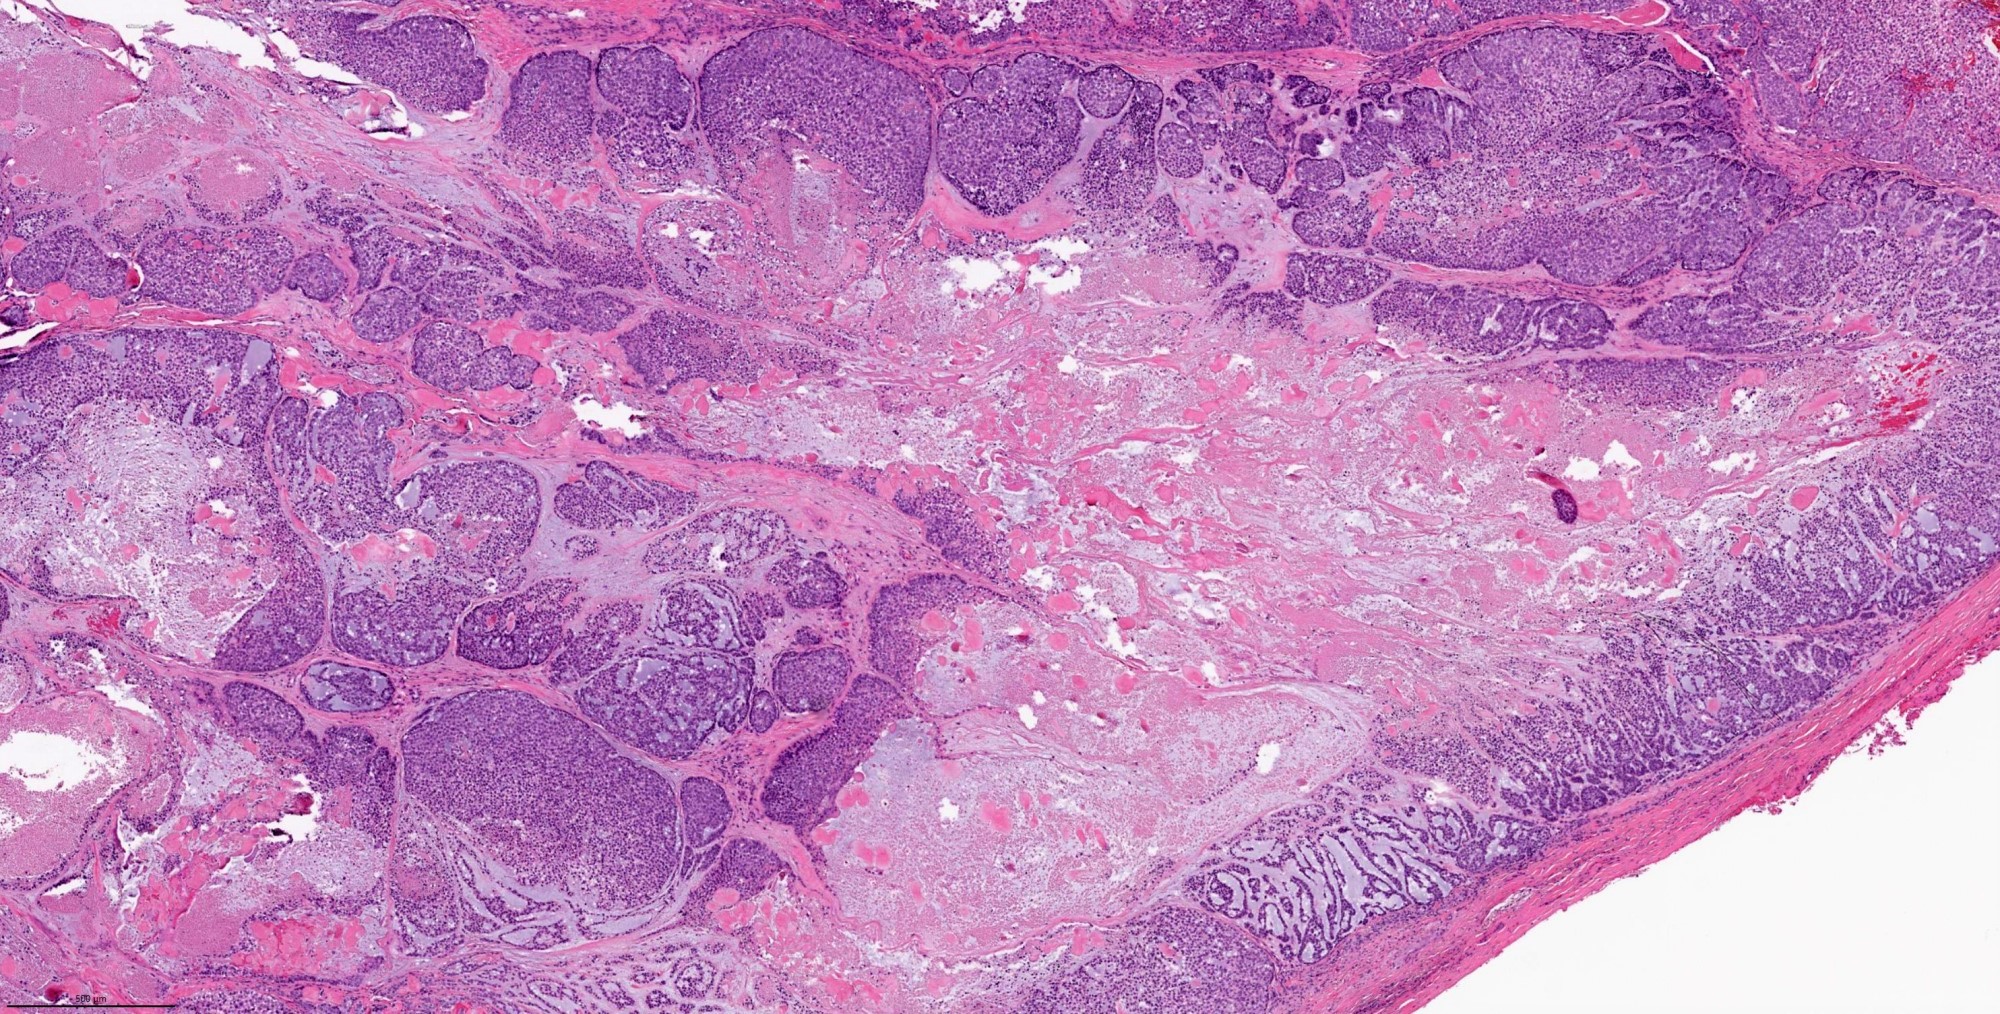

- Invasiveness is typically demonstrated as expansile invasive multinodular growth: myoepithelial carcinoma rarely shows infiltration of single cells / small clusters or desmoplastic reaction

- Nodules often have a hypocellular center with hyalinized stroma or bland necrosis surrounded by a hypercellular peripheral zone

- Composed (near) entirely of myoepithelial cells showing various cytologic features, including clear cell, epithelioid, plasmacytoid or spindle cell morphology

- Hyalinized, myxoid or myxochondroid stroma may be seen in myoepithelial carcinoma de novo and ex PA

- Common architectural patterns include solid, trabeculae, cords, nests and single cells

- Presence of pre-existing / residual pleomorphic adenoma component can be seen in myoepithelial carcinoma ex PA

Contributed by Abeer Salama, M.D. and Bin Xu, M.D., Ph.D.